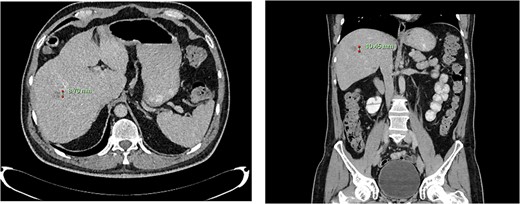

Computed tomography dated 15 January 2013 of the abdomen and pelvis measuring 10.50 mm (anterior–posterior) lesion at liver segment 5/6 in axial (left) and coronal (right) view.